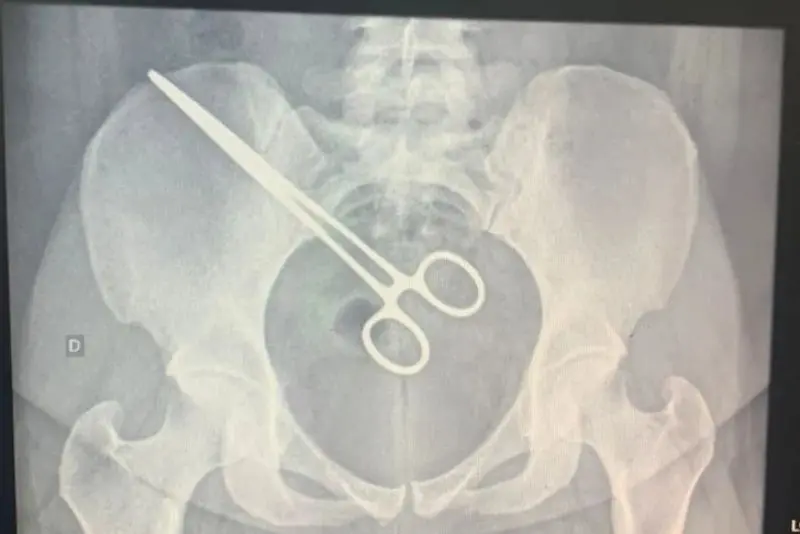

Uma mulher de 27 anos, precisou passar por uma cirurgia de emergência, para retirar uma pinça que foi esquecida na região pélvica após um procedimento de retirada de feto que aconteceu na Santa Casa de Araçatuba (150 quilômetros de Marília).

Ela passou mais de dois meses com o objeto no corpo e o caso só foi descoberto porque ao visitar o marido no Centro de Detenção Provisória de São José do Rio Preto o detector de metais indicou que a mulher estava com algo metálico no corpo.

A paciente foi até a Santa Casa, onde fizeram um exame de raio X e constataram que a pinça foi deixada dentro da paciente. A mulher foi internada novamente no hospital, para cirurgia de retirada do instrumento.